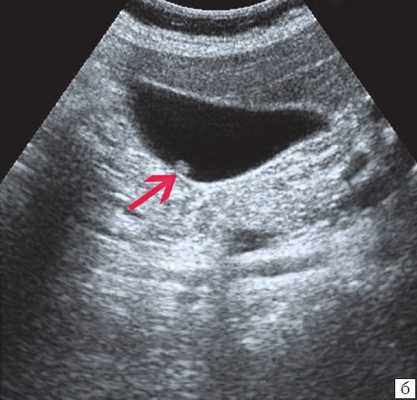

Ультрасонография является эффективным средством выявления полиповидной формы холестероза 6. Традиционной считается следующая сонографическая характеристика холестериновых полипов: неподвижные гиперэхогенные структуры, которые не дают акустической тени и прикрепляются к стенке желчного пузыря. Контуры таких образований, как правило, ровные, а размеры таких образований различны, чаще не превышают 10 мм (рис. 2).

б) Одиночный полип в желчном пузыре.

Однако, по некоторым данным, размеры холестериновых полипов могут быть более 20 мм. Кроме того, полипы больших размеров (в 7% от общего числа) могут иметь пониженную эхогенность и фестончатый контур.